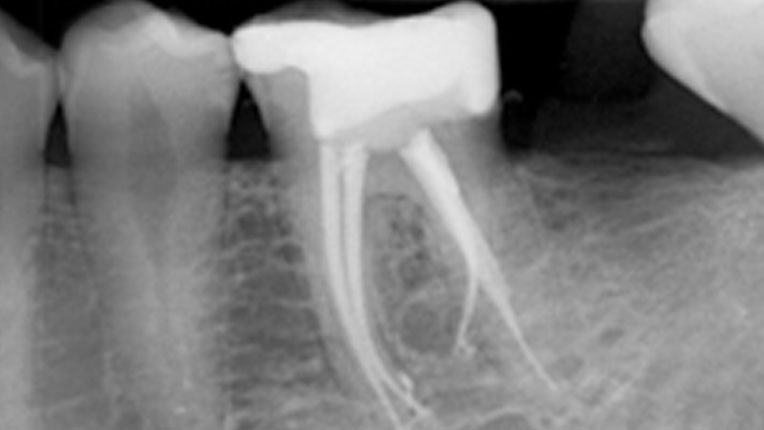

La Endodoncia es el procedimiento que se realiza para conservar el diente , que de otra manera tendría que ser extraido.

Disponemos del mejor Equipo en cuanto a personal y tecnología, ultimas tecnicas en Tratamientos sin dolor. Equipo de Endodoncia de Ultima Generación , sistema rotatorio con localizador integrado y Endodoncistas extensamente formados.

La mayoria de las Endodoncias se realizan en una sesion , es decir en una cita , existen determinados casos , por ejemplo cuando la infección es muy grande que es recomendable hacerlo en dos sesiones.

¿Por que en dos sesiones?, porque sino que no se puede obturar el mismo día con un material definitivo ya que puede causar mayores problemas, por eso es preferible en determinados casos hacerlo en dos sesiones.

Esto lo determina el Endodoncista , que es el especialista más cualificado para estos temas.